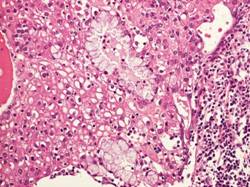

Carcinoma Mucoepidermoide

Neoplasia maligna delle ghiandole salivari caratterizzata da cellule mucoidi, intermedie, ed

epidermoidi, con cellule chiare, colonnari ed aspetti "oncocitoidi"

Aspetto istologico:

Il carcinoma mucoepidermoide è composto da vari tipi di cellule:

Cellule Basaloidi,

Cellule Intermedie,

Cellule Epidermoidi,

Cellule Colonnari,

Cellule Mucoidi,

Nell immagine sottostante è riportato un caso di carcinoma mucoepidermoide a basso grado che infiltra il tessuto osseo, per ricordare che anche le forme di basso grado hanno capacità invasiva. L intervento chirurgico tempestivo è importante.